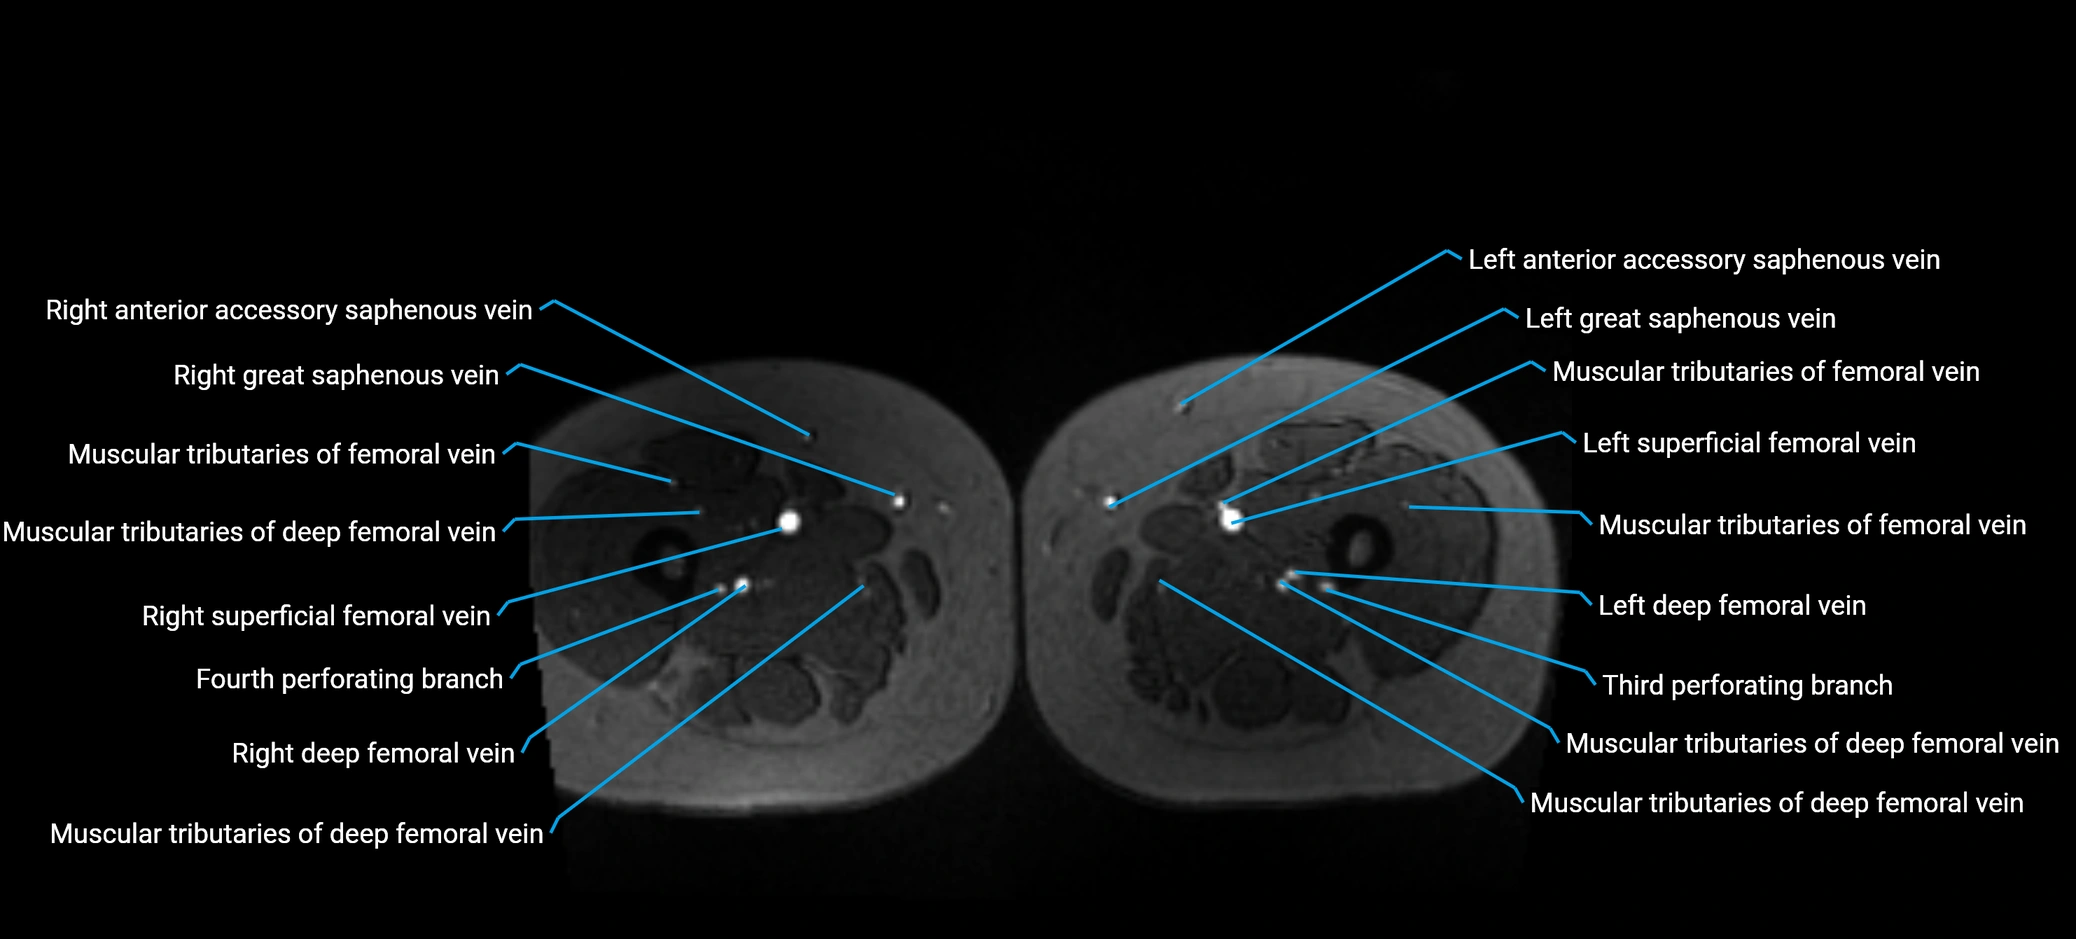

MRI image

image